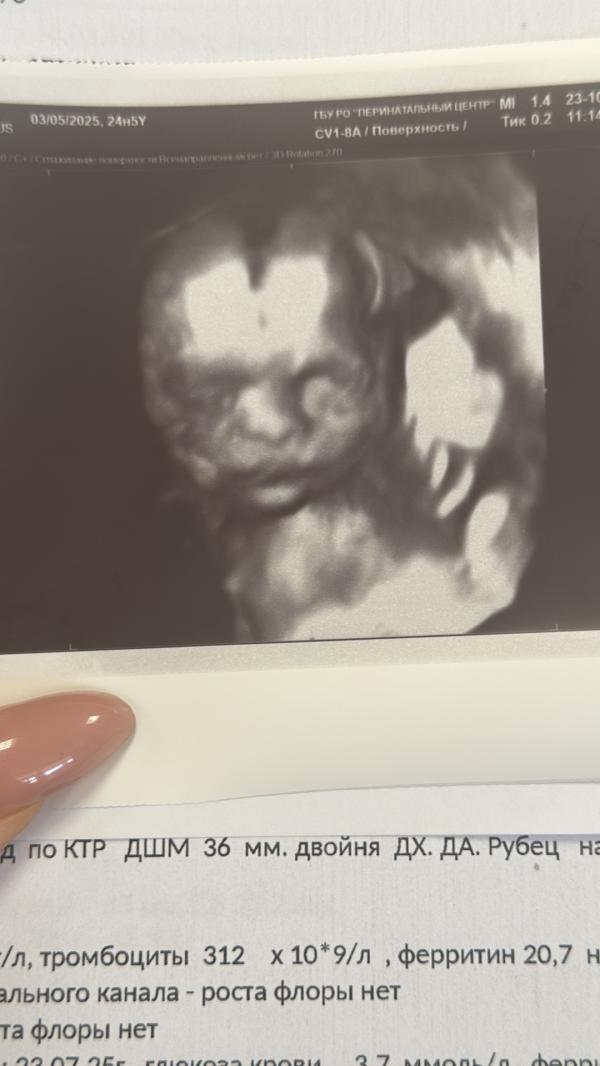

3D УЗИ двойни на 24 неделе: один малыш спрятал лицо

Ой девочки сходила на контрольное узи 🫠Слава богу все хорошо 🙏весим 740и 720 гр 🥰🫶сделала 3d ,получилось только одного поймать 😃второй закрыл лицо руками 🫣и не в какую не открывал 😀😀😀прям такие уже человечки 🥰🥰🥰